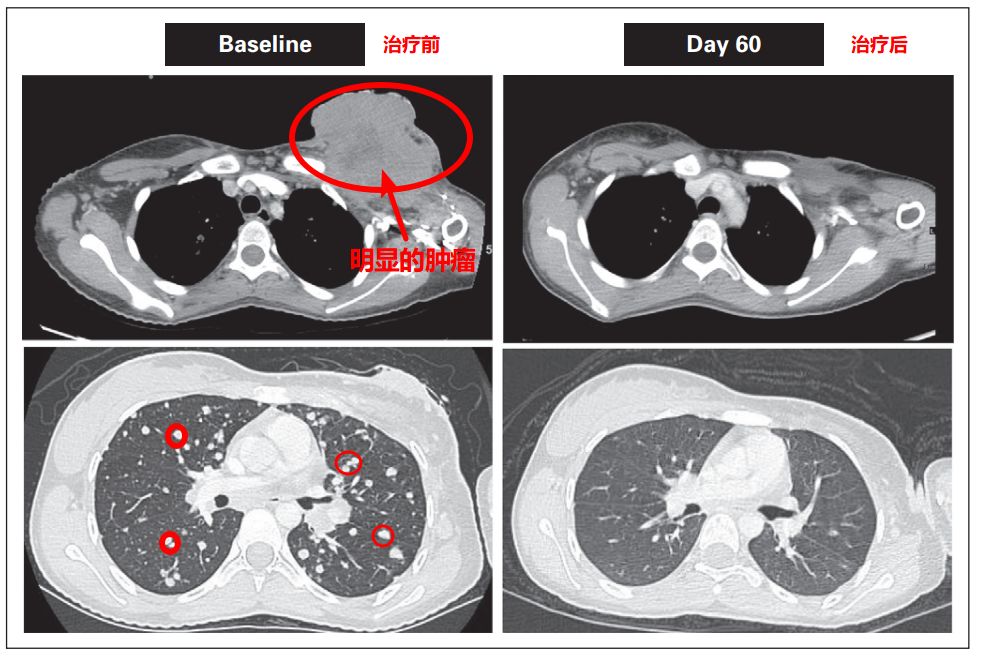

第一代TKR靶向药耐药后,两位患者尝试使用LOXO-195后,肿瘤再次快速缩小。患者治疗前后对比图如下,用药一个月后,耐药的肿瘤就再次减少甚至消失!